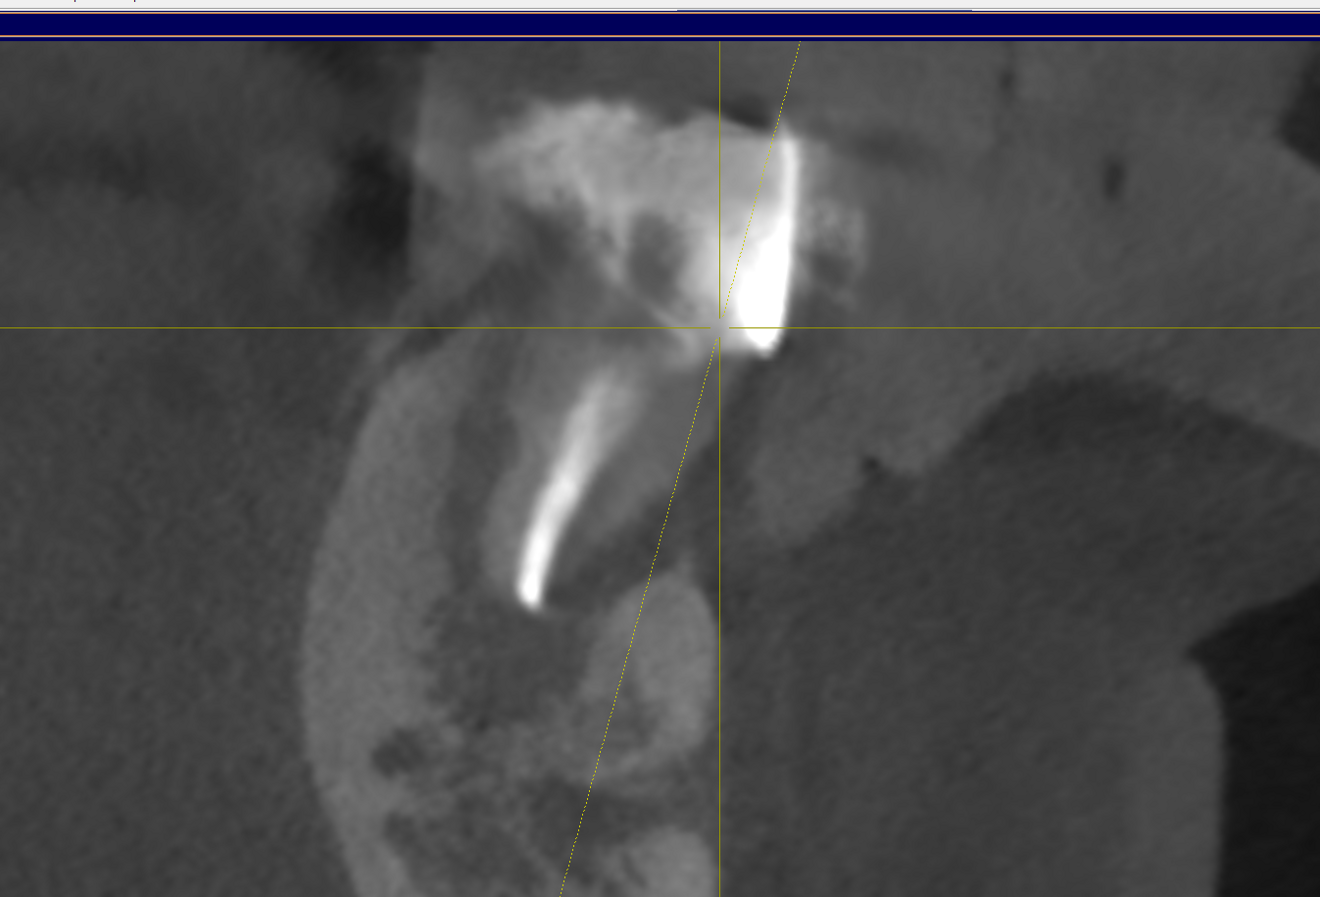

Figs. 2a–c: CBCT scan showing the failing endodontically treated tooth with an abscess.

The patient presented with multiple periapical radiolucencies associated with failing endodontically treated teeth, a horizontal root fracture and a failing long-span bridge (Fig. 1). A poor long-term prognosis was given to all the remaining mandibular teeth except tooth #46 (Fig. 2), and the treatment options, limitations and risks were reviewed thoroughly with the patient. The patient did not want a removable restoration and did not want to go a day without teeth and wanted to have biologically friendly materials used for treatment. It was decided to perform an immediate implant surgery and provide the patient with a stable temporary restoration to protect the healing implants for long-term success.